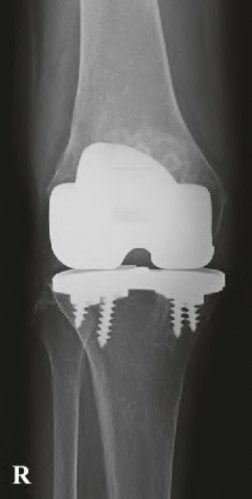

A 60-year-old male tennis player undergoes a unicompartmental knee arthroplasty (UKA) shown in Figures A and B. Which of the following statements regarding this procedure is true?

Figures A and B depict radiographs of a unicompartmental knee arthroplasty (UKA). UKA kinematics have been shown to most closely approximate native knee kinematics.

In an in vitro cadaver study, Patil et al found that TKA significantly changed knee kinematics while the unicompartmental replacement preserved normal knee kinematics.

Fisher et al performed a retrospective study comparing the short-term outcomes of small-incision unicompartmental knee arthroplasty (UKA) with standard total knee arthroplasty (TKA) in 91 consecutive patients older than 70 years. They found: 1) Blood loss was significantly more for the TKA group, as was the need for blood transfusion. 2) Patients with unicompartmental replacements had a much quicker return of function and discontinuation of pain medication. 3) While knee scores and ROM were similar preoperatively, both were better in the unicompartmental group at each postoperative time interval. 4) Narcotic use and length of hospital stay were also significantly less for the unicompartmental group. Therefore answers 2,3,4 and 5 are false.